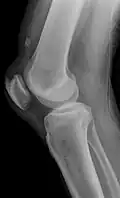

Quadriceps tendon rupture in plain X-ray: Incomplete rupture with haematoma in tendon. -